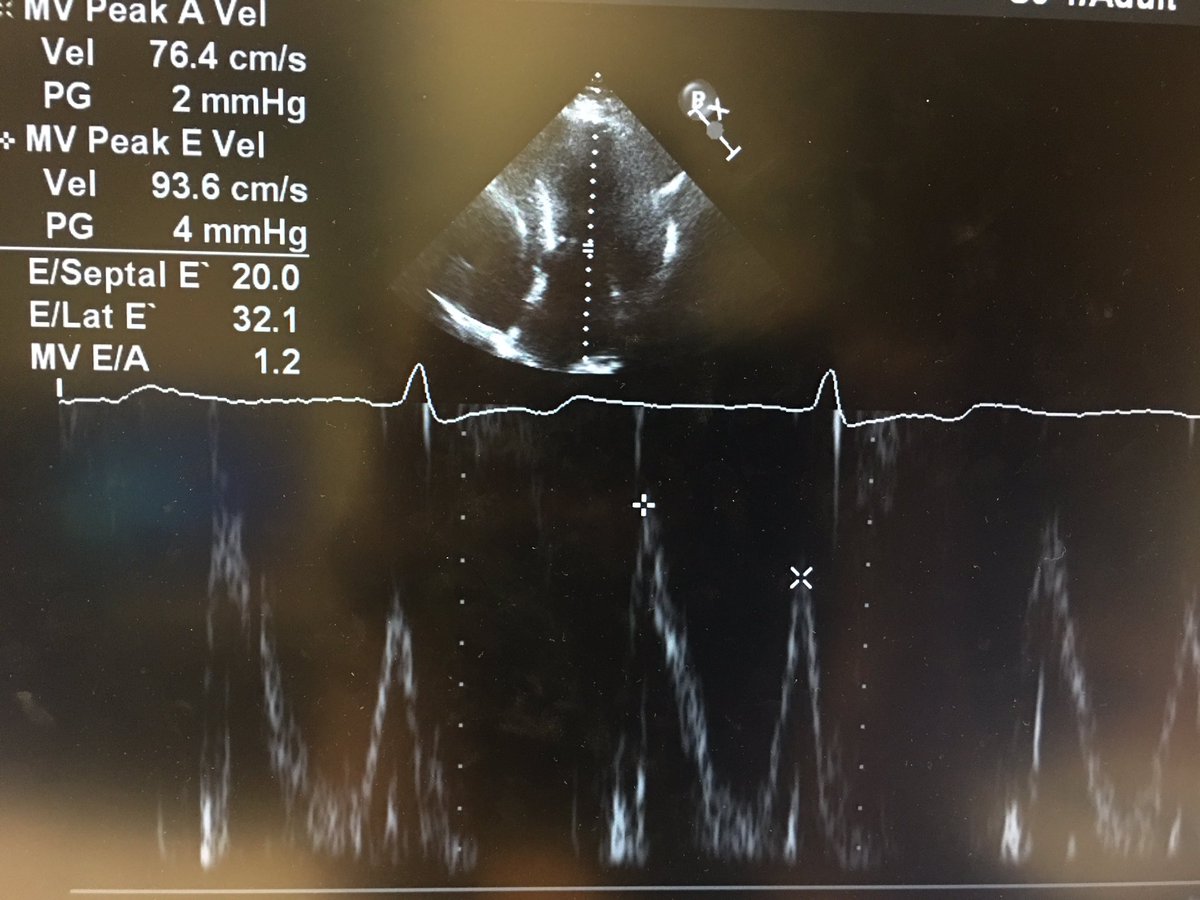

7) and lastly, perhaps unsurprisingly, there was pseudonormal filling with high filling pressures. #hocm #echofirst